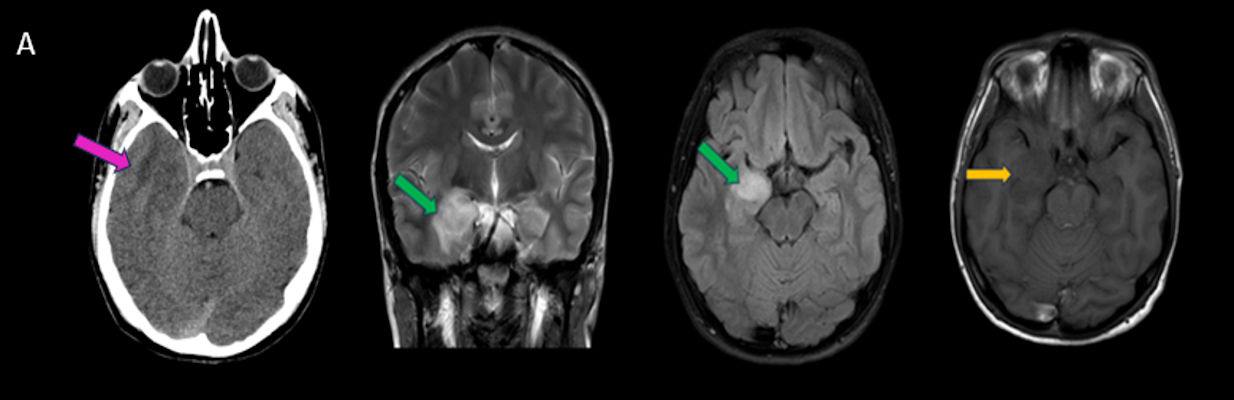

- A) Sağ temporal lob anteromedialinde silik sınırlı BT’de hipodens (ok), MRG’de T2AG ve FLAIR hiperintens (oklar), T1AG izo-hipointens (ok) sinyal özelliğinde ekspansil kitlesel lezyon izlenmektedir.

- BT: Spesifik olmayan kitle bulgularıdır. İzo-hipodens olarak izlenir. Kitle %35 oranında kalsifikasyon gösterebilir. Olgumuzda kalsifikasyon izlenmemiştir. Kemik remodelasyonu da eşlik edebilir.

- MRG: T1A serilerde solid komponent izo-hipointens, T2A serilerde genellikle hiperintens sinyalde görülür. Peritümöral T2/FLAIR hiperintens kitle ödemi oldukça nadirdir. T1 C+ görüntülerde solid komponentte değişken oranda kontrastlanma ,T2*(SWI) serilerde eğer kalsifikasyon eşlik etmekteyse buna bağlı blooming artefaktları görülebilir.